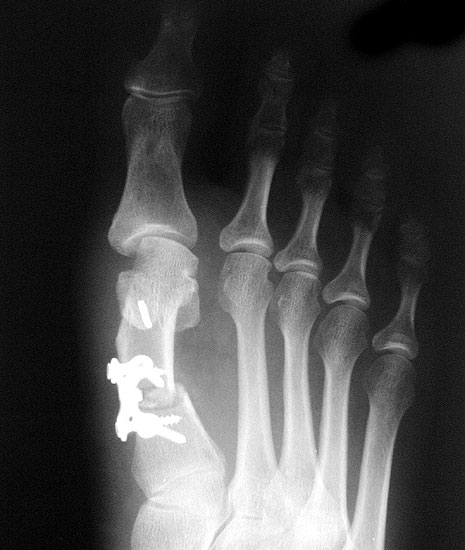

Beim Follow up nach 6 Monaten zeigte sich eine Korrektur des ersten Intermetatarsalwinkels (IMW) um durchschnittlich 9° (Range 4-15°) auf Normwerte (6,8° SD 1,3) (Abb. 21).

Gutes postoperatives Ergebnis mit physiologischem Intermetatarsale I-II Winkel nach open wedge Osteotomie.

Abbildung 21

In zwei Fällen kam es intraoperativ zu einem Bruch der lateralen Kortikalis. In einem Fall konnte durch die winkelstabile Platte eine ausreichende Stabilität erzielt werden, in dem anderen Fall wurde zusätzlich ein perkutaner Kirschnerdraht eingebracht, der nach 6 Wochen entfernt wurde. Eine stabile knöcherne Konsolidierung der Osteotomie ohne Korrekturverlust konnte in beiden Fällen erreicht werden. Die Analyse der Röntgenaufnahmen ergab eine Verlängerung des Os metatarsale I von durchschnittlich 1,8 mm (Range 1-4 mm).